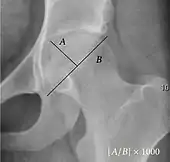

| Reimer's migration index[9] | ![]() |

The percentage of the femoral head that lies outside of the acetabular roof. It is also called the femoral extrusion index. | <25% |

| Tönnis angle | ![]() |